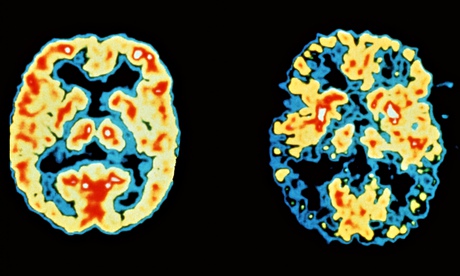

Brain scans of patients in good health (left) and with Alzheimer's disease (right), with high brain

Brain scans of patients in good health (left) and with Alzheimer's disease (right), with high brain activity in red and yellow and low activity in blue and black. Image: Dr Rober Friedland/Science Photograph: Dr Rober Friedland/Science